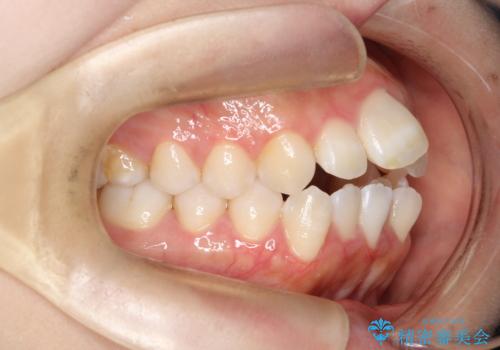

前歯のデコボコと開口を改善し、美しい口元へ

- 前歯のデコボコ(叢生)と、上下の歯が閉じない開口を主訴にご来院されました。精密な検査の結果、歯が並ぶスペースが不足しており、特に奥歯の咬み合わせが安定していないことが開口の原因と判明。患者様と相談し、上下左右の小臼歯を抜歯することでスペースを確保し、審美ワイヤー矯正で全体を整える治療計画を立案しました。これにより、見た目の改善だけでなく、機能的な咬み合わせも獲得することを目指します。

今回の矯正治療では、歯が並ぶスペースを確保するため、上下左右の小臼歯を抜歯しました。装置には目立ちにくい審美ワイヤーを使用し、見た目に配慮しながら治療を進めました。抜歯によってできたスペースを利用して歯を並べ、前歯のデコボコを解消。同時に、歯列全体を動かすことで、上下の歯がきちんと閉じる開口も改善しました。治療期間は約2年間。治療の結果、コンプレックスだった前歯のデコボコと開口が解消され、整った美しい歯並びと、しっかり咬める機能的な咬み合わせを獲得していただけました。